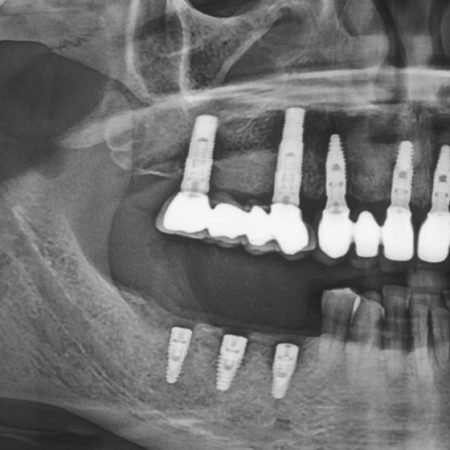

İmplant Röntgeni

Diş implantı tedavisinin uzun yıllar sorunsuz şekilde kullanılabilmesi için yalnızca cerrahi işlem değil, doğru görüntüleme ve düzenli kontroller de büyük önem taşır. Bu...

osstem implant röntgeni

PANORAMİK RÖNTGEN Diş röntgeni  ağızda dişlerin, kemik ve diş etlerinin birlikte görüntülendiği bir röntgendir. Diş hekiminin klinikte muayene ile görünmeyen kısımlarını...

DİŞ RÖNTGENİ RADYOGRAFİSİ:• Radyografiler, gözle yapılan muayenede fark edilemeyen çürük alanlarının (örneğin dişler arasındaki çürüklerin) görülmesini sağlar.• Mevcut olan...

Diş Röntgen Çeşitleri Ağız içi ve ağız dışı olmak üzere iki çeşit röntgen mevcuttur: Ağız içi: Film hasta ağzındadır. Ağız dışı: Film hasta ağzı...

Standart Panoramik Diş Röntgeni Dişler,çene kemikleri,temporomandibuler eklem ve maxiller sinüslerin incelenebileceği panoramik röntgendir.Magnifikasyon 1,3   1,5   1,7...